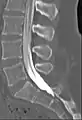

Myelography is a type of radiographic examination that uses a contrast medium to detect pathology of the spinal cord, including the location of a spinal cord injury, cysts, and tumors. Historically the procedure involved the injection of a radiocontrast agent into the cervical or lumbar spine, followed by several X-ray projections. Today, myelography has largely been replaced by the use of MRI scans, although the technique is still sometimes used under certain circumstances – though now usually in conjunction with CT rather than X-ray projections.

Water soluble non-ionic iodinated contrast agent is used nowadays and cause very little complication, unlike oil-based dye that was used previously which can cause arachnoiditis. However, history of allergy to iodine is contraindicated for the use of iodinated contrast.[1]

Contrast agent

Prior to the late 1970s, iofendylate (trade names: Pantopaque, Myodil) was the radiocontrast agent typically employed in the procedure. It was an iodinated oil-based substance that the physician performing the spinal tap usually attempted to remove at the end of the procedure. This step was both difficult and painful and complete removal could not always be achieved. The process of removing the contrast agent necessitated removing some of the patient's CSF along with it and the resulting deficiency of CSF gave rise to severe headache if the patient was raised from the prone position, requiring bed rest in the laying position. Moreover, iofendylate's persistence in the body might sometimes lead to arachnoiditis, a potentially painful and debilitating lifelong disorder of the spine.[3][4] This led to extensive litigation around the world since the substance was administered to millions of myelography patients over the course of more than three decades.[5] After water-soluble agents (such as metrizamide) became available it was no longer necessary to remove the contrast agent as it would eventually be absorbed into the body although the water-soluble agent sometimes gave rise to severe headaches if it got into the head, requiring bed rest in the upright position.